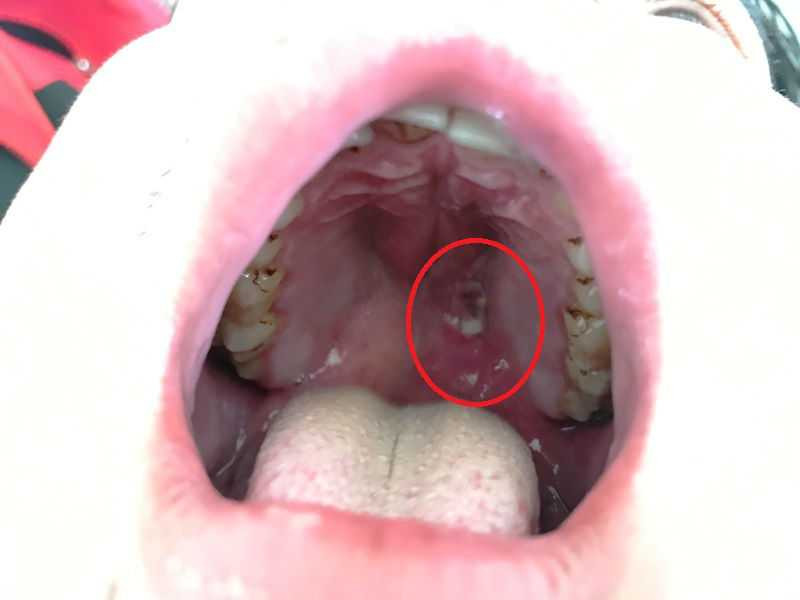

Vị trí viên đạn bi trong vòm họng nam bệnh nhân

Trong lúc đang thổi, anh Phong vô tình dùng tay bóp vào bộ phận cò khiến viên đạn bay ra, găm thẳng vào vòm họng, miệng đầy máu.